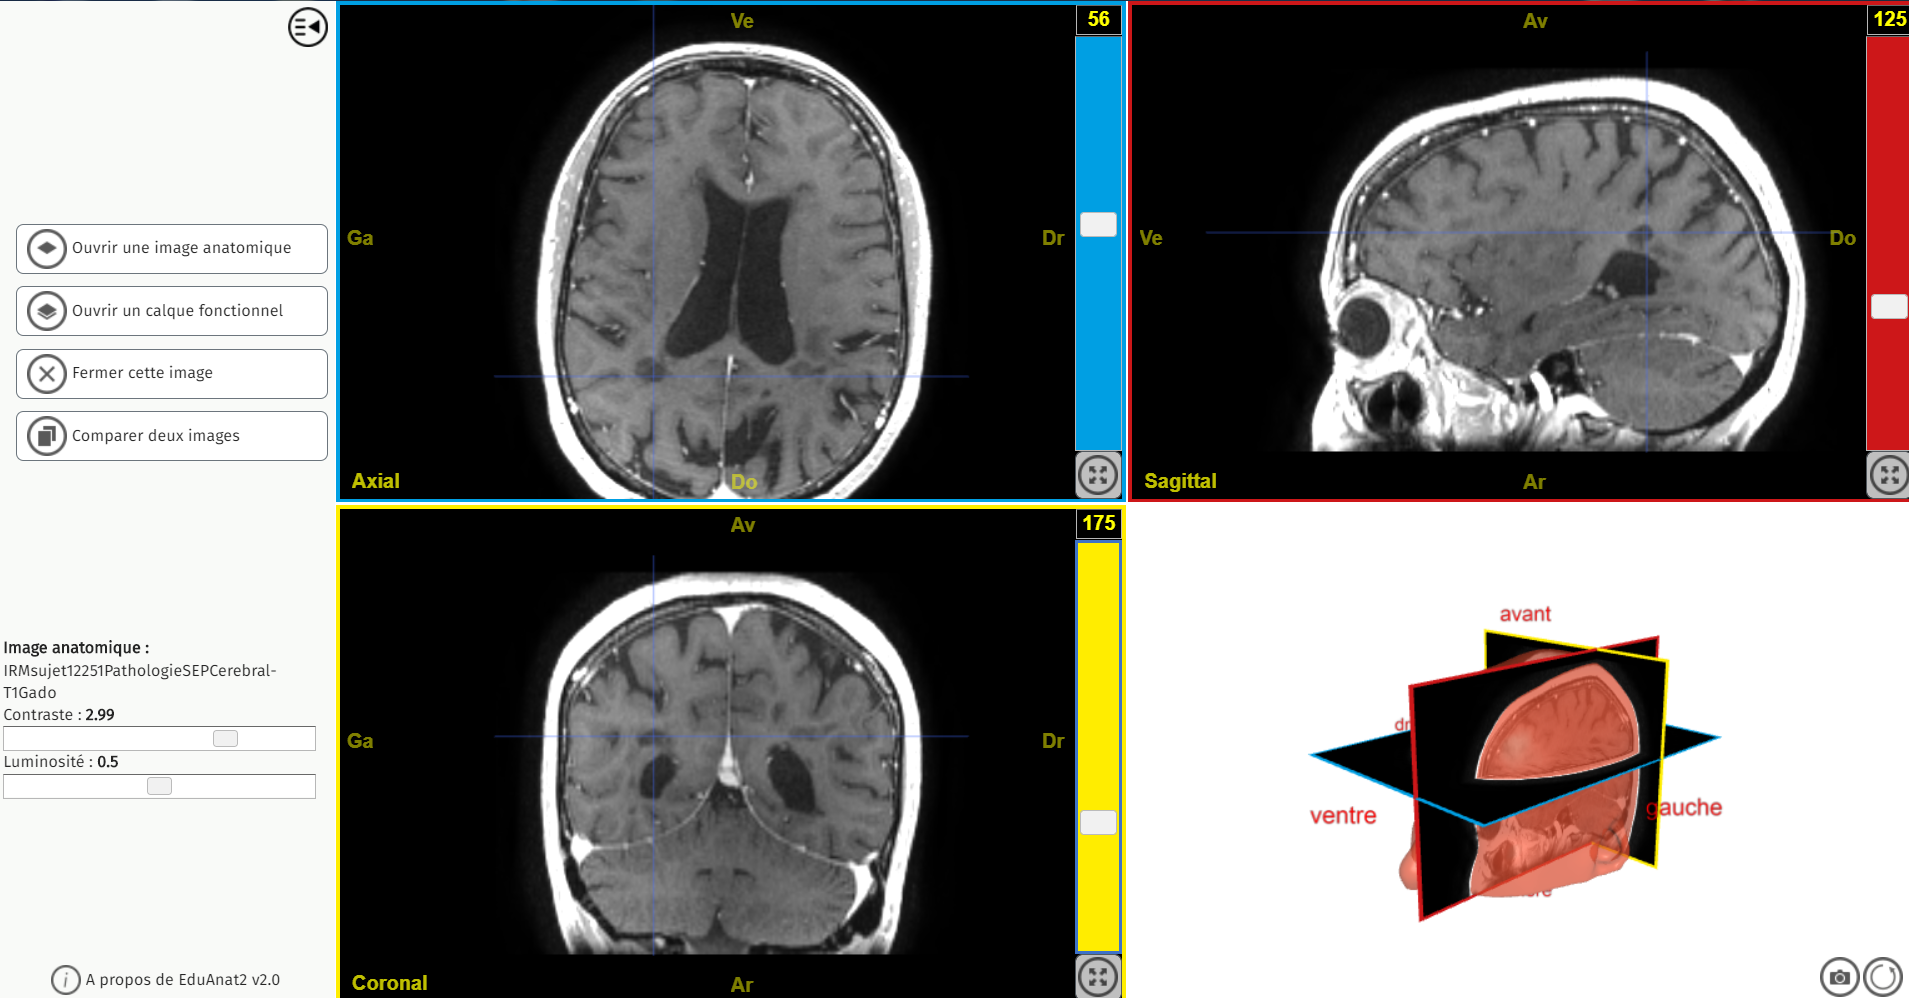

IRMsujet12251PathologieSEPCerebral T1Gado